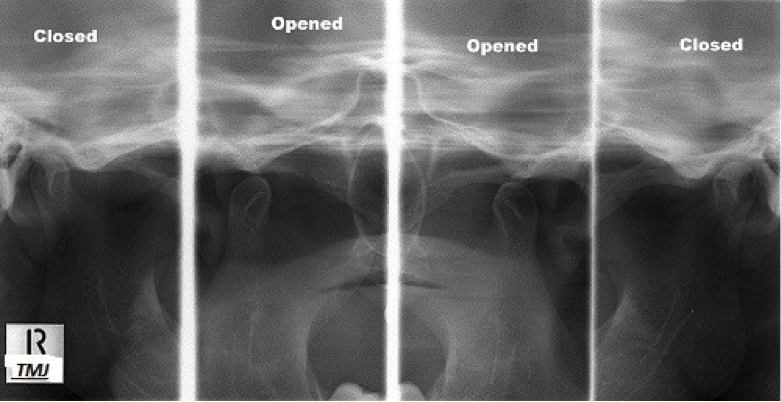

TEMPROMANDIBULAR JOINT

Tempro mandibular joint (TMJ) syndrome is pain in the jaw joint that can be caused by a variety of medical problems. the TMJ connects the lower jaw (Mandible) to the skull (Temporal bone) in front of the ear ,certain facial muscles control chewing. Problems in this area can cause head and neck pain, facial pain and ear pain.